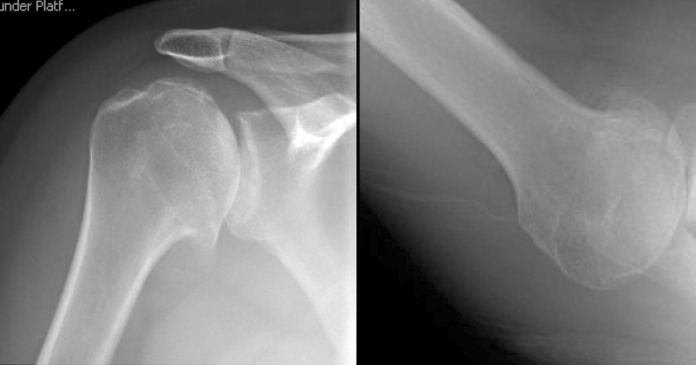

A 40 year old very physically active man presented with pain, stiffness and feelings of instability of the right shoulder.  His axially “truth” view showed almost complete posterior decentering of the huneral on a retroverted biconcave glenoid.

He came back to the office fourteen years after his ream and run procedure reporting full function of this shoulder for all this athletic activities. His 14 year films (below) show centering of the anteriorly eccentric humeral head on the glenoid with no evidence of glenoid wear or erosion.